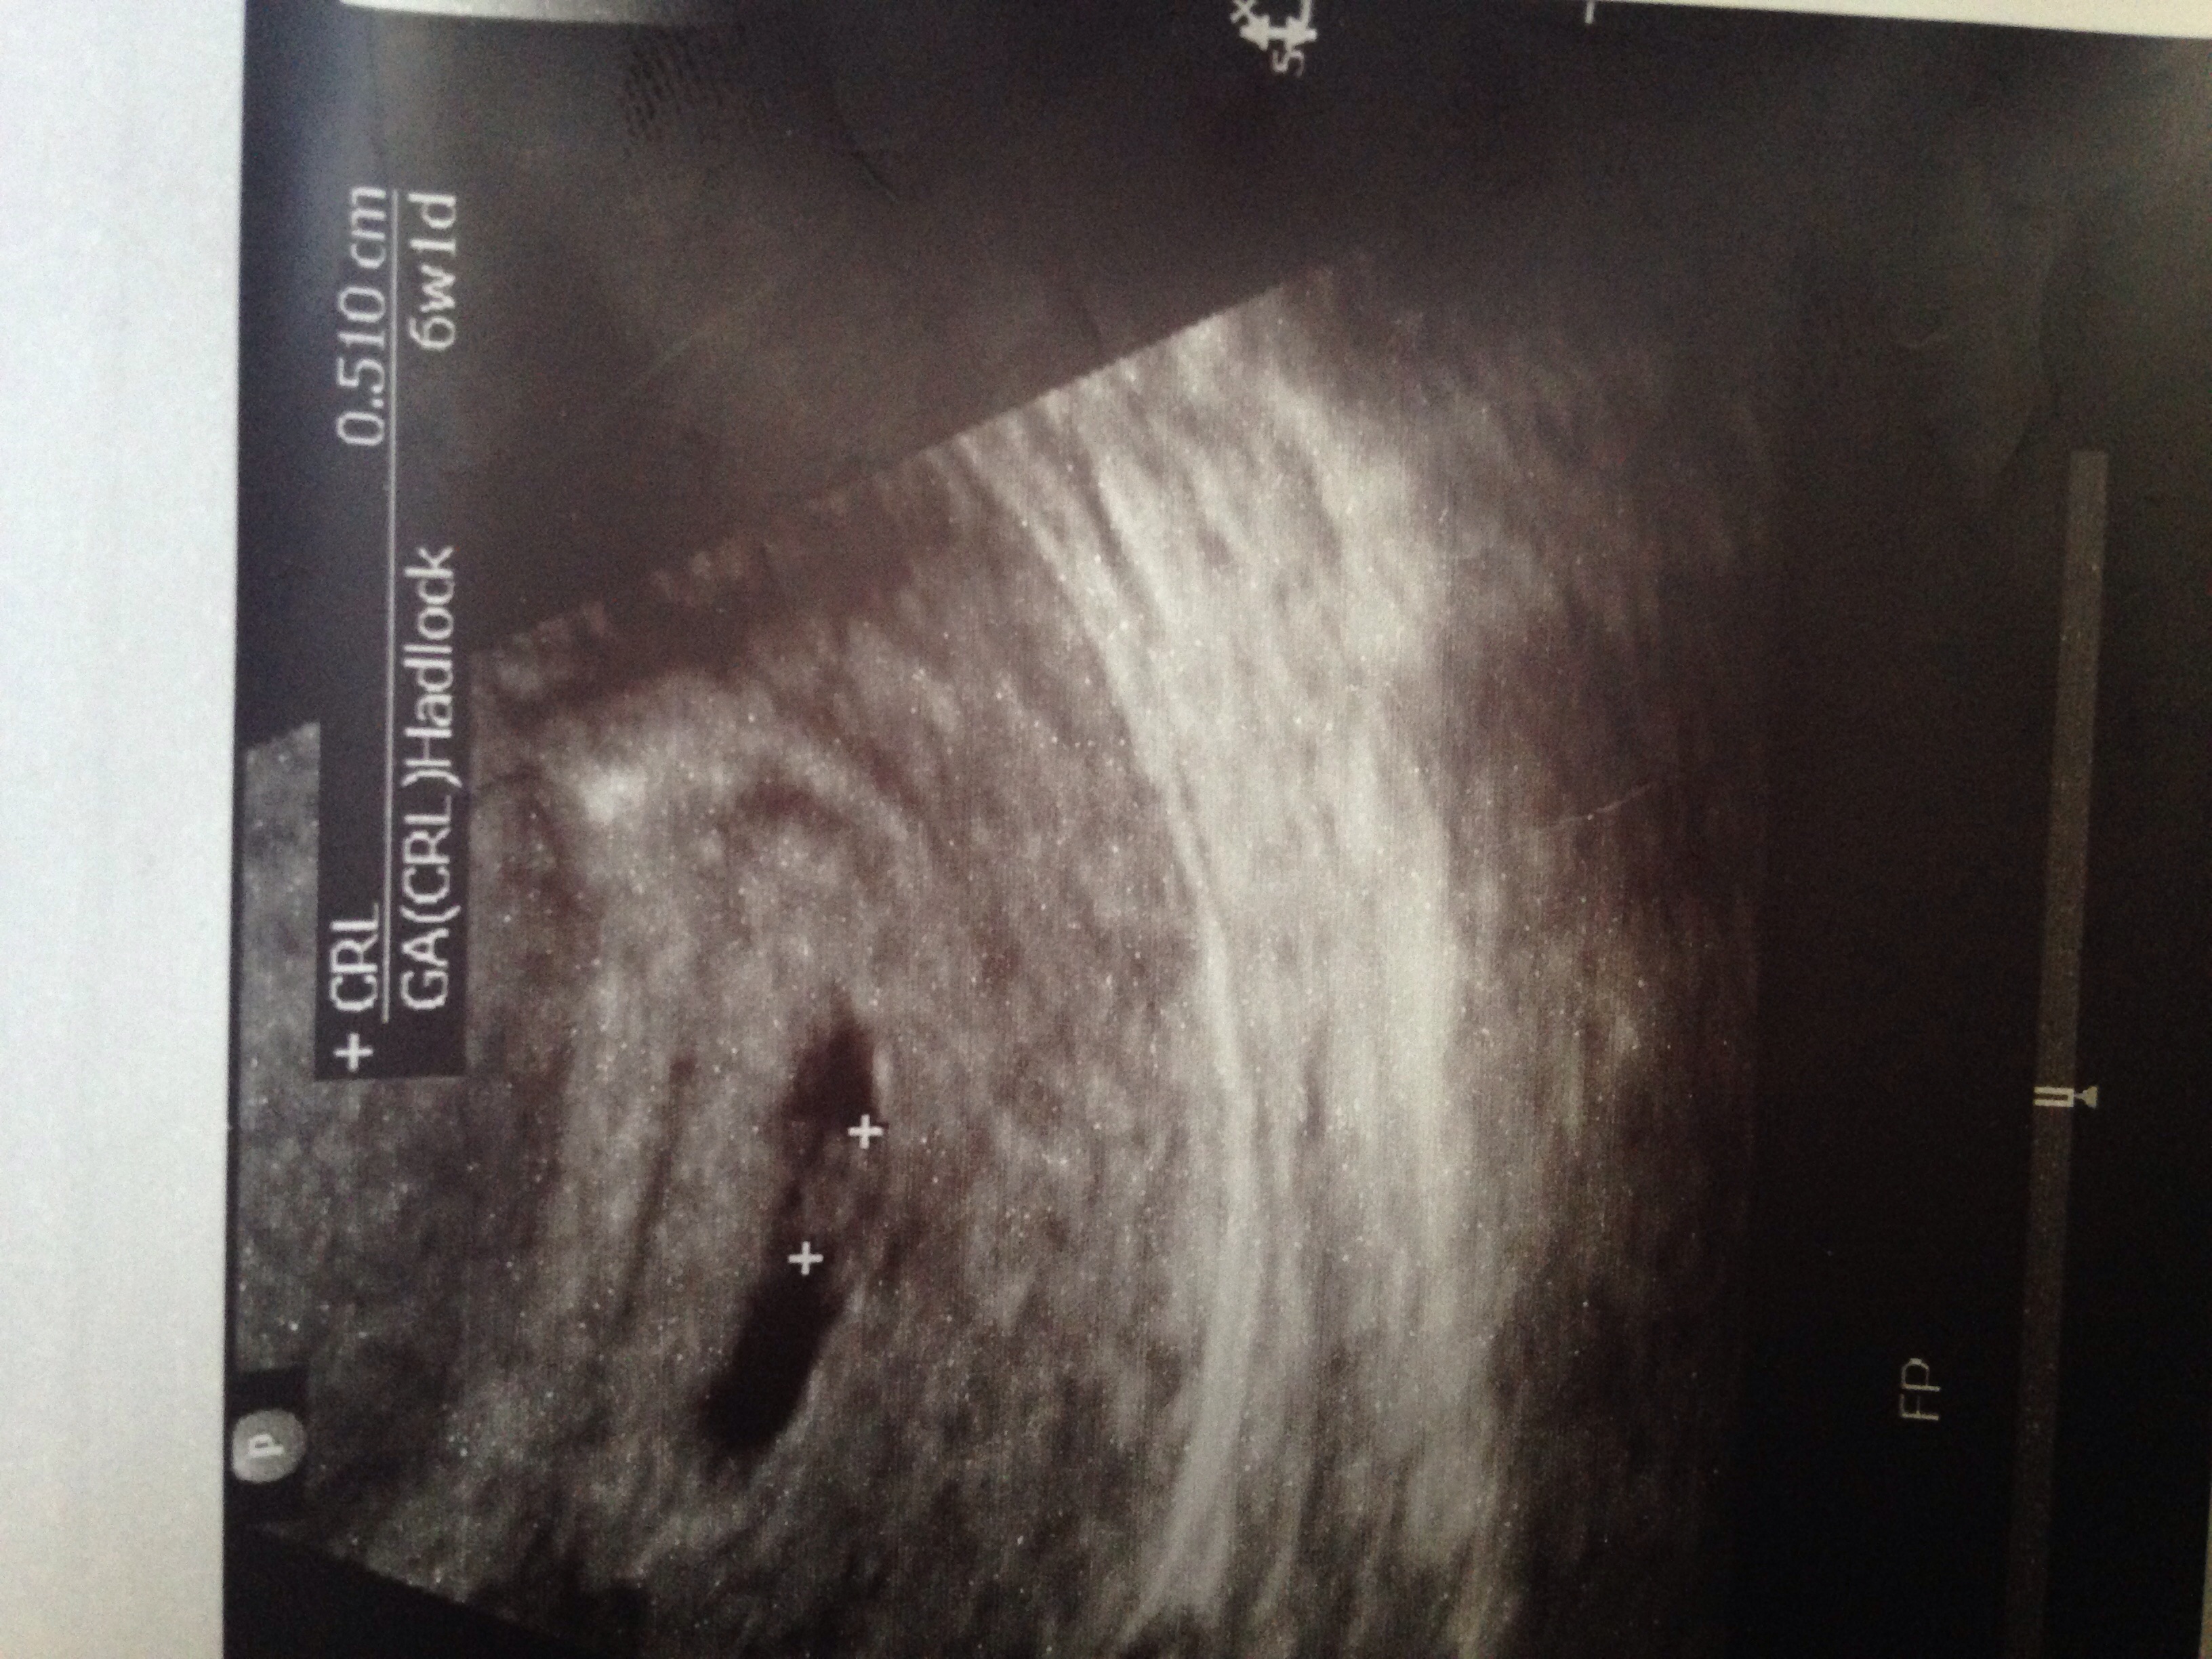

Attachment 31223I would love for someone to tell me girl or boy based on the theory. This was a transvaginal ultrasound. Thank you in advance!!!

I don't know much about the Ramzi theory but your scan picture looks exactly like my DS2 At 7week ultrasound picture. Hope this helps at all x